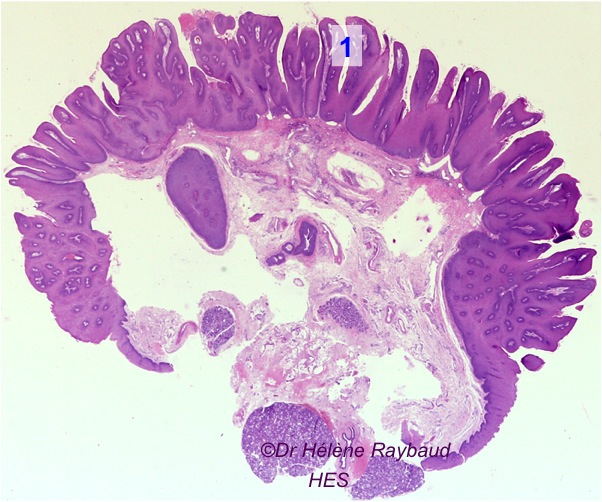

Le papillome buccal, généralement associé au virus du papillome humain (VPH), soulève de nombreuses questions concernant ses causes, ses traitements et ses. Salut tout le monde, Je mesure 36 m tout droit, j'ai eu mal (angine streptococcique) il y a 2 mois et en ouvrant la bouche, j'ai vu une chose blanche… J'ai été diagnostiqué en février 2021, d'un papillomavirus qui c'est logé dans la partie inférieur de la langue, après 3 chimios et 33 radiothérapies, qui se sont déroulées entre avril et mai de la même année, je n'ai plus de signe de cancer.

Papillome inversé avec extension inhabituelle à l’oropharynx à propos d’un cas La. J'ai été diagnostiqué en février 2021, d'un papillomavirus qui c'est logé dans la partie inférieur de la langue, après 3 chimios et 33 radiothérapies, qui se sont déroulées entre avril et mai de la même année, je n'ai plus de signe de cancer. Bonjour, j'ai une sorte de boule en haut à droite du palais, elle est dure mais quand je touche elle me fait mal, je l'ai remarqué se matin je crois que ça fait 2~3 jour que je l'ai est-ce que je doit m'inquiètez, faire quelque chose ?